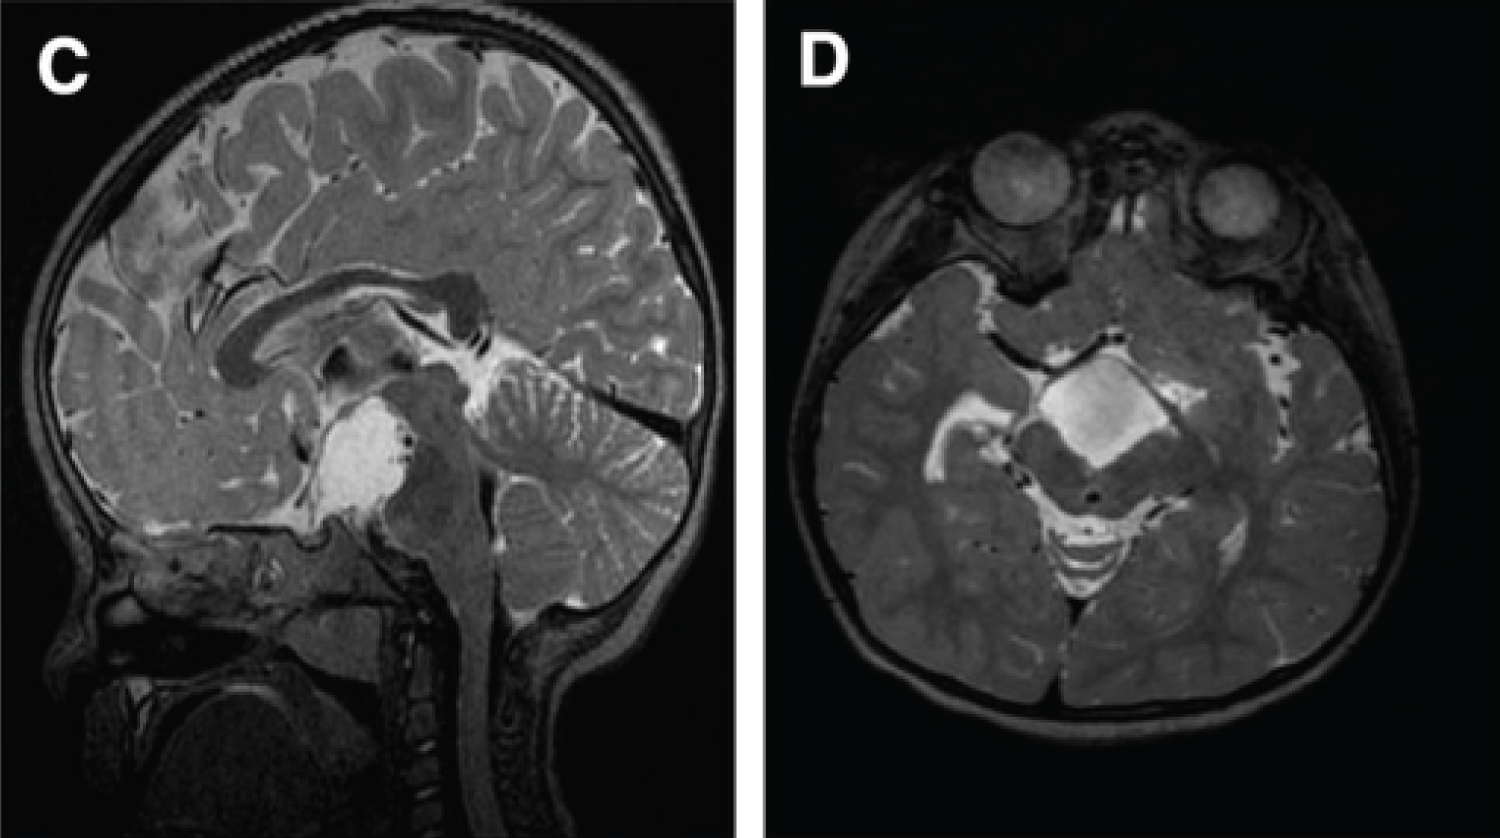

The next MRI showed a reduction of the size of the ventricles and an absence of mass effect of the cyst. The patient was discharged on day....

The follow-up MRIs showed a normal size of the ventricles, a decrease in size of the cyst and a patency of the stomy. One of those MRIs showed a migration of the proximal catheter, under the skin, without any consequence on the size of the ventricles or cyst. We then removed the VP shunt.

The patient has a normal psychomotor development. The last clinical check-up was at 1 year and a half and the cyst and ventricles are stable. A long-term follow-up is planned.